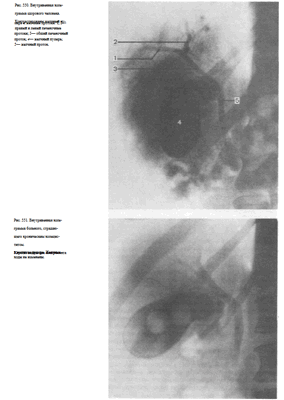

Выделительная холеграфия (холецистохолангиография) осуществляется путем внутривенного введения 20—40 мл 50—70% трийодированного контрастного вещества. Эта методика позволяет изучить состояние не только желчного пузыря, но и желчных ходов. Желчные протоки оптимально контрастируются в течение первых 30 мин, а желчный пузырь — через 1 '/г ч.

При выделительной холецистохолангиографии на снимках отчетливо видны печеночные протоки, общий желчный проток, пузырный проток, а также желчный пузырь (рис. 550). Интенсивность выделения препарата печенью характеризует и ее выделительную функцию.

Выделительная холеграфия дает возможность выявить холестериновые камни как желчного пузыря, так и расположенных в желчных протоках, а также исследовать желчные пути после холецистэктомии (рис. 551).

Для изучения состояния общего желчного и печеночных протоков применяют интраоперационную холангиографию. При этом хирург вводит водорастворимое контрастное вещество непосредственно в желчные пути посредством пункции. Чаще всего пунктируют пузырный или общий желчный проток в терминальном отделе. После измерения давления в желчных путях из них отсасывают некоторое количество содержимого и осторожно, под небольшим давлением, вводят 10—20 мл контрастного вещества.

Не удаляя иглы с помощью переносного или палатного аппарата производят рентгеновский снимок (кассету подкладывают под больного заранее) и подвергают его срочной фотообработке. Перед рентгенографией хирургические инструменты стремятся расположить вне проекции желчных путей (рис. 552).